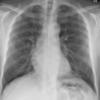

Normal PA Female

Date: 12/06/2014

Views: 6016